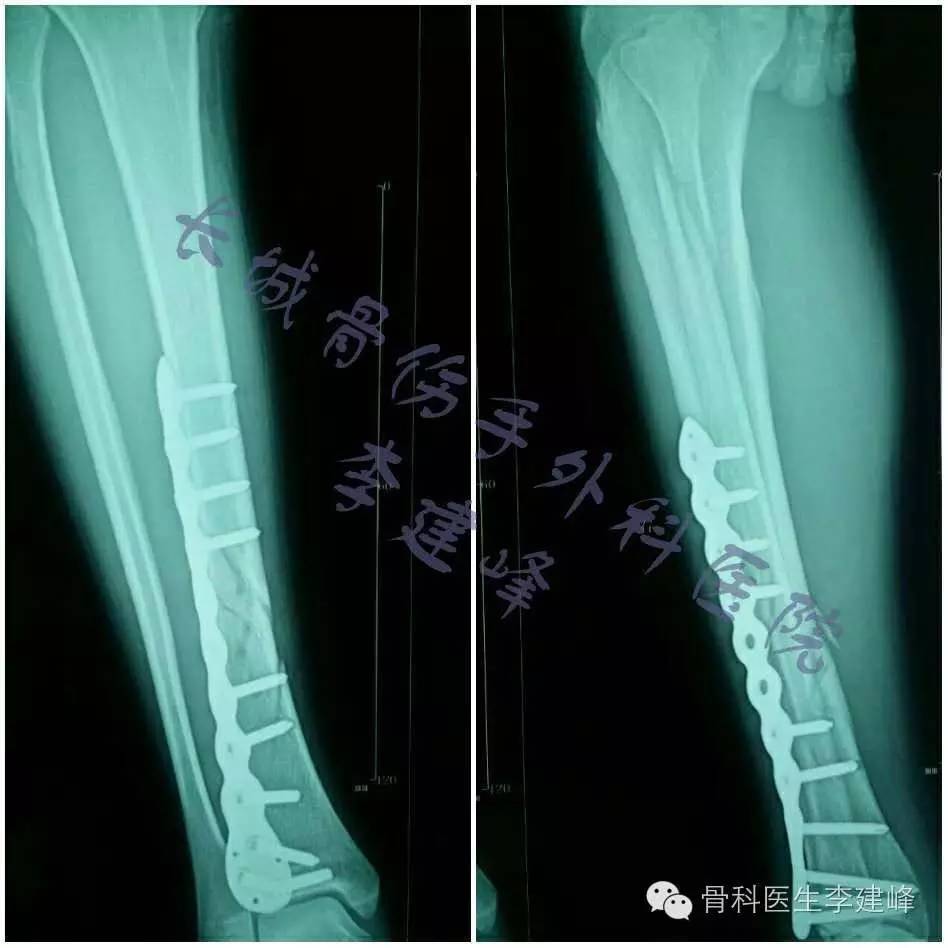

术后